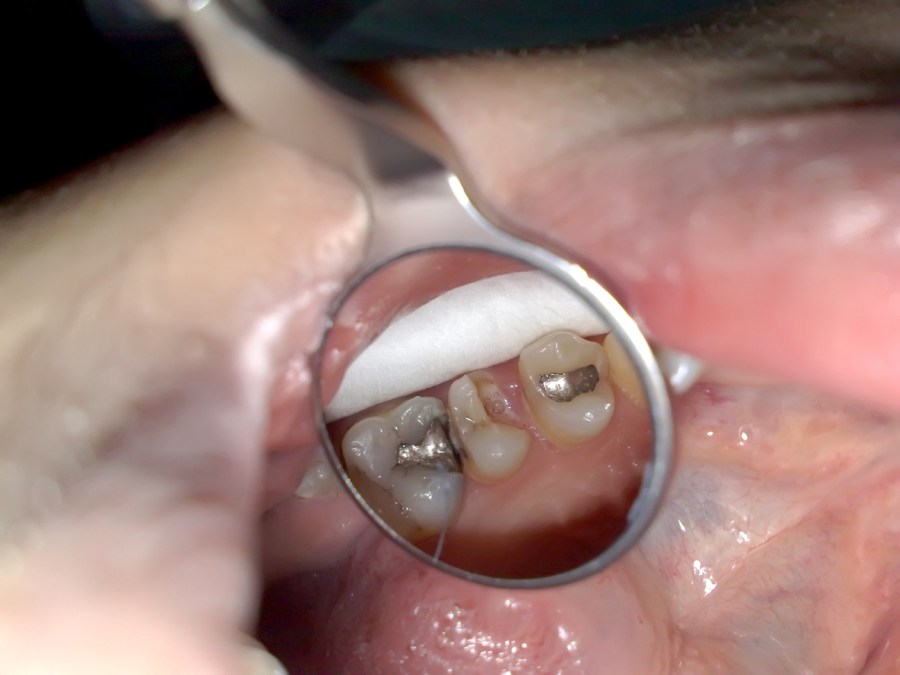

When Metal Onlay Failed and Endo Do the Rest